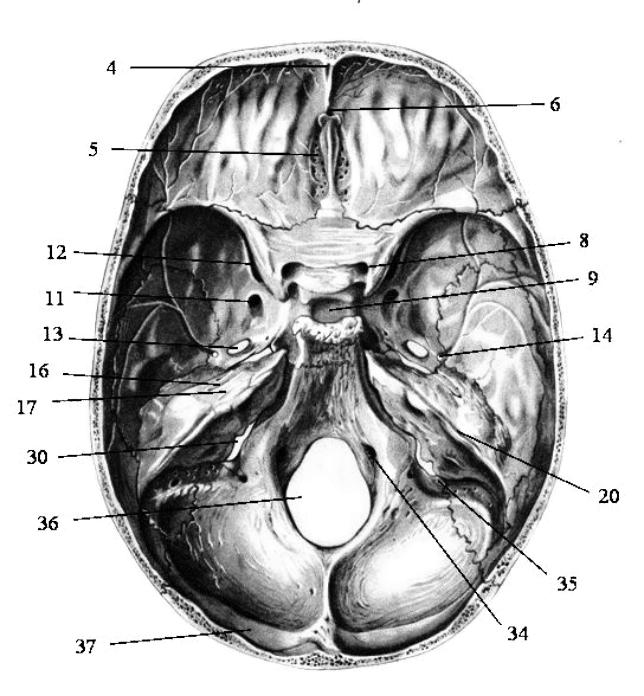

Анатомические детали: Фотографии топографии черепа с нижнего вида

Раздел: Альбом идей